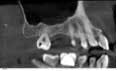

Case 1: Osteotome sinus lift with simultaneous implant placement

A 53-year-old female with a medical history of hypothyroidism, seasonal allergies, and asthma taking Synthroid and Singula presented to my office with pain in No. 3, failed root canal therapy, and a fracture. The tooth was deemed hopeless and extraction and implant placement was treatment planned. Under local anesthesia, tooth No. 3 was sectioned into three pieces and extracted. The sockets were debrided, filled with gel foam, and closed with chromic gut sutures. Healing was uneventful. The patient did not return for two years for follow-up. A CT scan was taken, which confirmed that approximately5 mm of bone remained below the floor of the sinus. After reviewing the options with the patient, a treatment plan of an internal sinus lift (osteotome), bone graft, platelet-rich fibrin (PRF) and simultaneous implant placement was agreed upon. Under local anesthesia, a full thickness flap with two vertical releasing incisions was performed at tooth No. 3 site. A trephine bur was used to a depth of 4 mm. An osteotome was then employed to infracture the bone core, which remained attached to the Schneiderman membrane. A bone graft consisting of DFDBA, anorganic bovine bone, and PRF was used in the osteotomy to increase the vertical bone height using sequential osteotomes. After sufficient elevation, a 7x9 tapered implant was placed on low speed to 50% of the implant depth. The remaining placement of implant was done with a hand torque on 50 ncm to allow for further expansion of the alveolar housing. A healing abutment was placed using the principles of platform switching. Healing was uneventful, and integration was successful.

Case 1: Implant and osteotome bone graft through the socket with Southern Implant